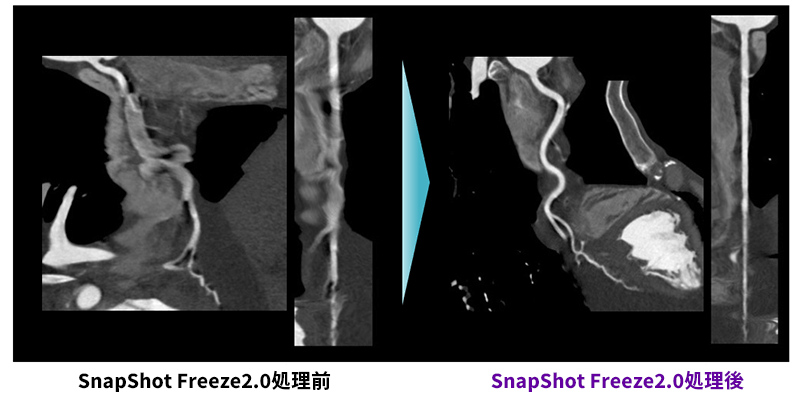

検査前は心拍数が120bpmを超えて、意思疎通困難・呼吸停止不可という患者の条件が非常に悪い中での撮影。最適心位相にて自動的に再構成された画像においてもブレが大きく、静止画像は全く期待できないと感じましたが、SnapShot Freeze2.0にて処理を行った画像はブレが大きく改善され大変きれいな画像であり、苦労することなく画像解析をすることが出来ました。

RevolusionCT_Sapporotokusyuukai_03.png